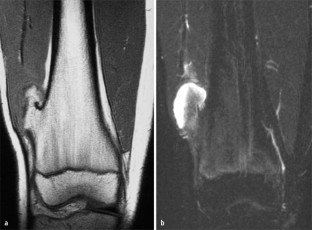

MRI morphology of bone tumors and tumor-like lesions

Für das Staging und die Charakterisierung von Knochentumoren und tumorähnlichen Läsionen ist in der Magnetresonanztomographie (MRT) der Einsatz von Spinechosequenzen erforderlich. Die MRT hat nur einen geringen Stellenwert in der Bestimmung der Dignität. Obwohl viele Knochentumoren und tumorähnliche Läsionen eine vergleichbare Morphologie in dieser bildgebenden Modalität aufweisen, können einige Tumorentitäten mittels MRT recht zuverlässig diagnostiziert werden. Hierzu zählen Knorpeltumoren, die solitäre und aneurysmatische Knochenzyste, der Riesenzelltumor, fetthaltige Läsionen und bis zu einem gewissen Grad auch das Osteoidosteom und das Osteoblastom. Es werden praktische Tipps gegeben, wann bei Tumorverdacht die MRT eingesetzt werden sollte, wie bei einem zufällig bei einer MRT gefundenen Tumor die Untersuchung modifiziert werden sollte und welcher Tumor vorliegen könnte.

Spin-echo sequences are mandatory at MRI for staging and characterization of bone tumors and tumor-like lesions. MRI is of minor value in the estimation of the malignant potential of an osseous lesion. Although many bone tumors and tumor-like lesions present similar morphology at MRI, some entities can be diagnosed with good reliability. These include chondrogenic tumors, solitary and aneurysmal bone cysts, giant cell tumors, lesions containing fatty tissue and, to a certain extent, osteoid-osteomas and osteoblastomas. Practical advice is given regarding when to perform a MRI study in cases of tumor suspicion. Further advices are given for cases a tumor is found incidentally at a MRI study, how to modify the study and which kind of tumor may be present.